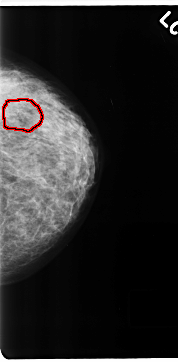

C_0199_1.LEFT_CC

LEFT_CC LINES 4696 PIXELS_PER_LINE 2312 BITS_PER_PIXEL 12 RESOLUTION 50 OVERLAY

FILE: C_0199_1.LEFT_CC.OVERLAY

TOTAL_ABNORMALITIES 1

ABNORMALITY 1

LESION_TYPE CALCIFICATION TYPE PLEOMORPHIC DISTRIBUTION CLUSTERED

ASSESSMENT 5

SUBTLETY 4

PATHOLOGY MALIGNANT

TOTAL_OUTLINES 1

BOUNDARY